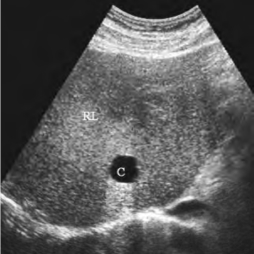

图23-10 肝囊肿声像图

肝脏右叶囊肿(C),圆形无回声区,边界清楚,壁薄

1.肝内见圆形或椭圆形无回声区,边界清楚,壁薄,内部极清晰,后方回声增强(图23-10)。